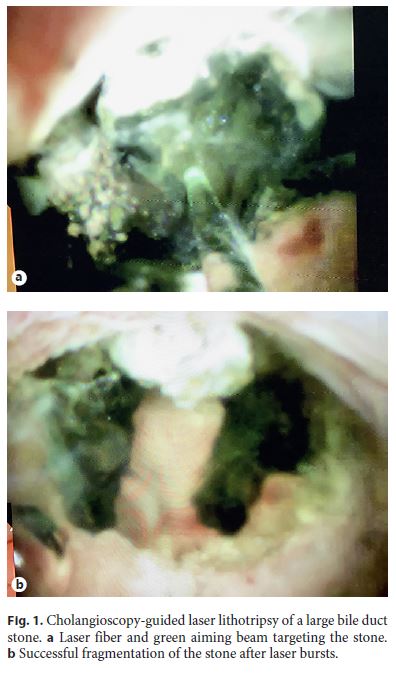

Holmium Laser Technology. We used this technology (Auriga XL 50W, model 4007; Boston Scientific) with a dedicated 365-µmdiameter fiber (LightTrail Fiber; Boston Scientific), with energy levels set at 8001,500 mJ and a frequency of 815 Hz. For biliary stones, most of the times, we used a frequency of 12 Hz and an energy level of 1,2001,500 mJ. For pancreatic stones, we used a frequency of 810 Hz and an energy level of 8001,200 mJ. The tip of the laser fiber has a green aiming beam (brightening regulated), which was used to target the stone under direct vision. With the probe tip 12 mm away from the stone, and under continuous or intermittent saline irrigation, laser bursts were delivered through the aqueous medium until stone fragmentation was deemed complete (Fig. 1).

Bipolar EHL System. We used this system (Autolith Touch Biliary EHL System; Boston Scientific) with a dedicated 1.9-Fr 375- cm EHL probe (Boston Scientific) which was optimized for use with the SGDS. The probe was used with the following parameters: low, medium, or high power depending on the technical challenge, and 510 pulses per foot pedal activation.

The probe is used only in aqueous medium under continuous or intermittent saline irrigation. The probe has no aiming beam and is used with the probe tip touching or 12 mm away from the stone. The choice of the cholangioscopy-guided lithotripsy system depended on system availability and on the preferences of the endoscopist. When performing cholangioscopy, the SpyScope was inserted through the papilla and advanced to the common bile duct or cystic stump towards the stone of interest, with endoscopic vision and intermittent fluoroscopy. When deemed necessary, the cholangioscope was advanced over a stiff 0.025-inch guidewire. After direct visualization of the stone, the guidewire was changed by the 1.9-Fr EHL probe. When using the holmium laser technology, the fiber was preloaded into the cholangioscope’s 1.2-mm working channel, which allows the simultaneous presence of the laser fiber and the 0.025-inch guidewire. For pancreatoscopy, the SpyScope was always advanced over the 0.025-inch guidewire. The energy of the laser fiber or of the EHL probe was delivered until stone fragmentation was deemed complete. Fragmented stones were removed with conventional extraction devices at the discretion of the endoscopist, which may have included mechanical lithotripsy. In case complete ductal clearance was not achieved in 1 session, 1 or more plastic biliary or pancreatic stents were inserted until the next session.